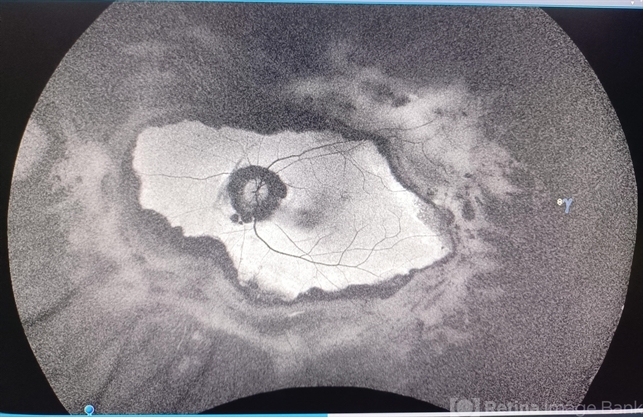

- chorioretinal scar

- Sanauddin Samejo, Burjeel Hospital, Abu Dhabi, UAE.

Fundus camera

Optos Silverstone - Description

- A patient came in to Clinic of Dr Madhav Rao (VR Surgeon)